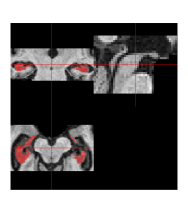

Figure 8 displays the posterior probability map for hippocampus inclusion, along with the point-wise standard deviations. The highest probabilities of inclusion are near the centers of the two regions. There is considerable uncertainty about the edges. If a researcher were only interested in the hippocampal volume for the patient, these probabilities could be used directly to estimate the volume, as discussed below.

Unlike the other automatic segmentations, the fully Bayesian label fusion produces measures of uncertainty in the form of a posterior probability distribution that can be used to derive marginal distributions of any quantity of interest, as we discuss below. Further, our proposed model also has the ability to estimate the spatially-varying reliability parameters for each atlas. Supplementary Figure 6 displays the sensitivity and specificity maps for one selected atlas. We see smooth decay of sensitivity between regions of high agreement and low agreement with the manual segmentations. Since the sensitivity is conditional on the voxel truly being part of the structure (), the model is only capable of estimating sensitivity in areas where it estimates a high probability of the voxel truly being part of the structure. The fields return to their prior means as they move away from the structure estimate. Similarly, the specificity values are estimated to be very high away from the targeted structure, where all atlases agree on the voxels being excluded.